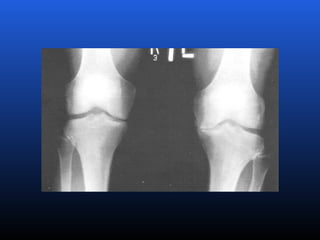

EPIDEMIOLOGIA

 Particularmente, na articulação do joelho,

evidenciou-se, que 52% da população adulta

apresenta sinais radiológicos da doença,

sendo que, somente 20% destas apresentam

alterações consideradas como graves ou

moderadas.

RADIOLOGIA

No início da doença não se observam anormalidades.

Com seu desenvolvimento, observam-se:

 Diminuição do espaço intra-articular

 Esclerose subcondral (eburnação)

 Osteófitos;

 Erosão e anquilose óssea (pseudocistos ósseos).

EPIDEMIOLOGIA  Particularmente, naarticulação do joelho, evidenciou-se, que 52% da população adulta apresenta sinais radiológicos da doença, sendo que, somente 20% destas apresentam alterações consideradas como graves ou moderadas.

RADIOLOGIA No início dadoença não se observam anormalidades. Com seu desenvolvimento, observam-se:  Diminuição do espaço intra-articular  Esclerose subcondral (eburnação)  Osteófitos;  Erosão e anquilose óssea (pseudocistos ósseos).